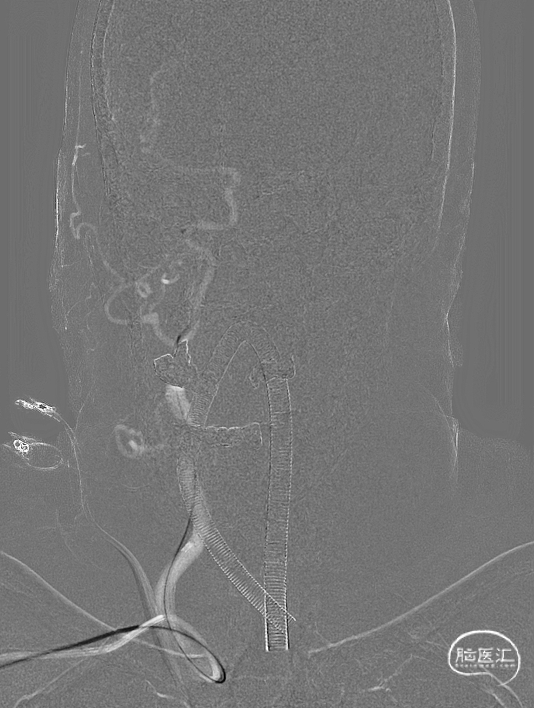

原位释放支架后造影。

术后即刻影像及患者术后情况

术后即刻正侧位及3D造影:造影示血流明显改善(术前造影未显影的大脑前动脉出现),远端血管无缺失。LCI-CT未见出血。麻醉复苏后查体无新发神经功能缺损。